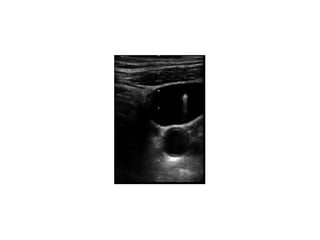

Figure 1: Ultrasound image of the right side of the neck showing absence

of internal jugular vein. CA: Carotid artery

5353 the right sideof the neck carefully using a portable ultrasound (US) machine (IMAGIC Agile, Kontron Medical, WA, USA) with a linear, high frequency transducer (7.5–12 MHz). Care was taken to apply minimal pressure on the probe to prevent collapse of the IJV. Imaging showed a single pulsatile vessel, which was non compressible suggestive of the carotid artery with right sided IJV has also been reported in a 12-year-old boy during US evaluation prior to attempted cannulation.[4] In another report, IJV agenesis was discovered during neck dissection. Patients who require removal of IJV due to disease infiltration may have potentially life-threatening complicationofcerebraledemaiftheotherIJVisaplastic.[5] Figure 1: Ultrasound image of the right side of the neck showing absence of internal jugular vein. CA: Carotid artery Figure 2: Ultrasound image of the left side of the neck showing normal anatomy. CA: Carotid artery; IJV: Internal jugular vein